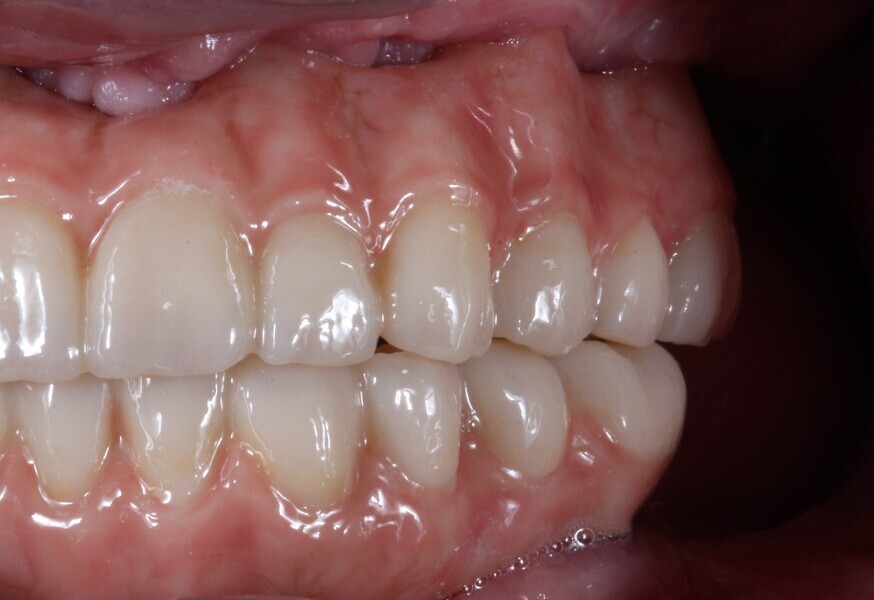

In this case, the final prostheses were fabricated using monolithic KATANA Zirconia YML (Kuraray Noritake Dental). This high-quality material offers excellent strength, durability and aesthetics for dental restorations. The staining process was performed using CERABIEN ZR FC Paste Stain (Kuraray Noritake Dental) to achieve a natural appearance and blend seamlessly with the patient’s existing dentition. PANAVIA V5 in the shade Opaque and CLEARFIL CERAMIC PRIMER PLUS (both Kuraray Noritake Dental) were used to cement the bases (Elos Accurate Hybrid Base H Non-Engaging compatible with Straumann Standard and Standard Plus 4.8 mm diameter, regular neck implants; Elos Medtech; Figs. 15–22).

Fig. 19: Final prostheses, right side view. The cervical parts were stained with the shade Cervical 2, the incisal two thirds of the anterior teeth with the shade Grayish Blue and the mamelons with the shade Mamelon Orange 1.

Fig. 20: Final prostheses, left side view.